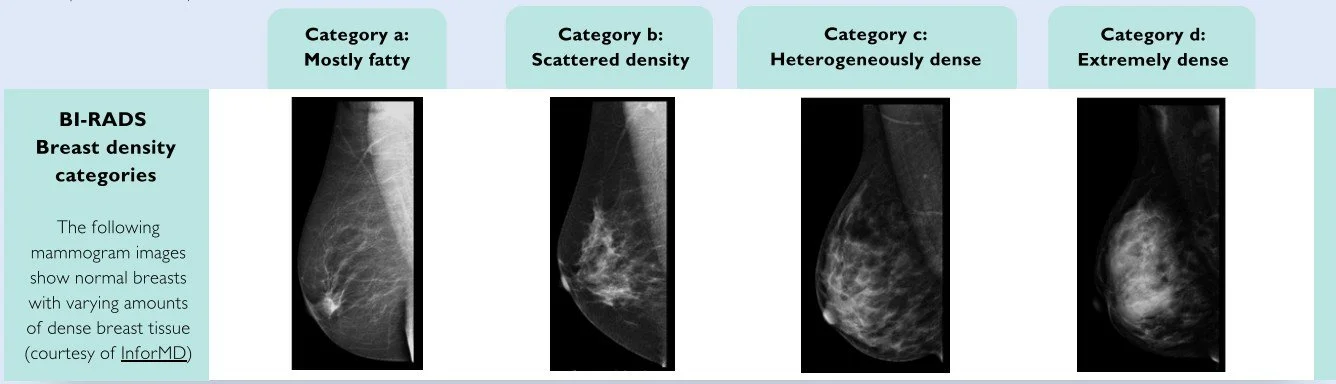

Breast Density is reported as A,B,C or D.

The sensitivity of screening mammography (that is, the percentage of women with cancer who attend screening and are correctly identified as having cancer) is approximately 90% for women with low breast density (classified as BI-RADS a or b), 84% for women with dense breasts (BI-RADS c) and 64% for women with extremely dense breasts (BI-RADS d)

As a group, women with BI-RADS category a have around half the risk for breast cancer than women with BI-RADS category b, while those with BI-RADS category c and d have 1.6-fold and 2.6-fold higher risk, respectively, than women with BI-RADS category b.